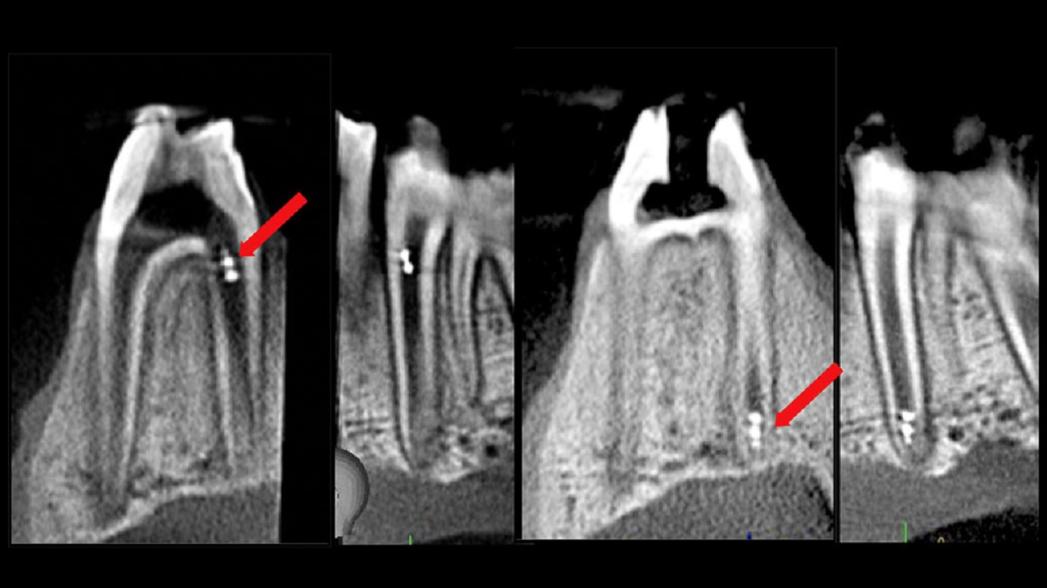

Лечение корневого канала зуба — не самый приятный опыт, но если оно не удалось, и инфекция повторилась, то обычно требуется повторная процедура, которая не менее неприятна и сопровождается раздражением и разочарованием. Чтобы избежать этого сценария, лучше всего удалить как можно больше инфекционного материала у основания зуба, но это пространство узкое и труднодоступное для оценки его состояния.

Ученые из университета Пенсильвании (США) разработали систему микророботов для стоматологии, которая может помочь в разрушении биопленки, доставке лекарств и извлечении образцов, и все это в ограниченном пространстве корневого канала. Стоматологам бывает трудно определить, удалили ли они весь инфекционный материал из корневого канала, и неспособность сделать это обычно приводит к рецидиву инфекции. Это пространство труднодоступно и его трудно продезинфицировать должным образом, поэтому исследователи обратились к микророботам в качестве решения проблемы.

На данный момент исследователи из Пенсильванского университета протестировали микророботов на изготовленных при помощи 3D-принтера копиях человеческих зубов, которые они "заселили" различными эндодонтическими бактериями. Они успешно ввели рой микророботов в корневой канал, нарушили культивированную биопленку, удалили образец бактерий, а затем подтвердили с помощью микроскопии, что все наночастицы были извлечены из канала после процедуры.